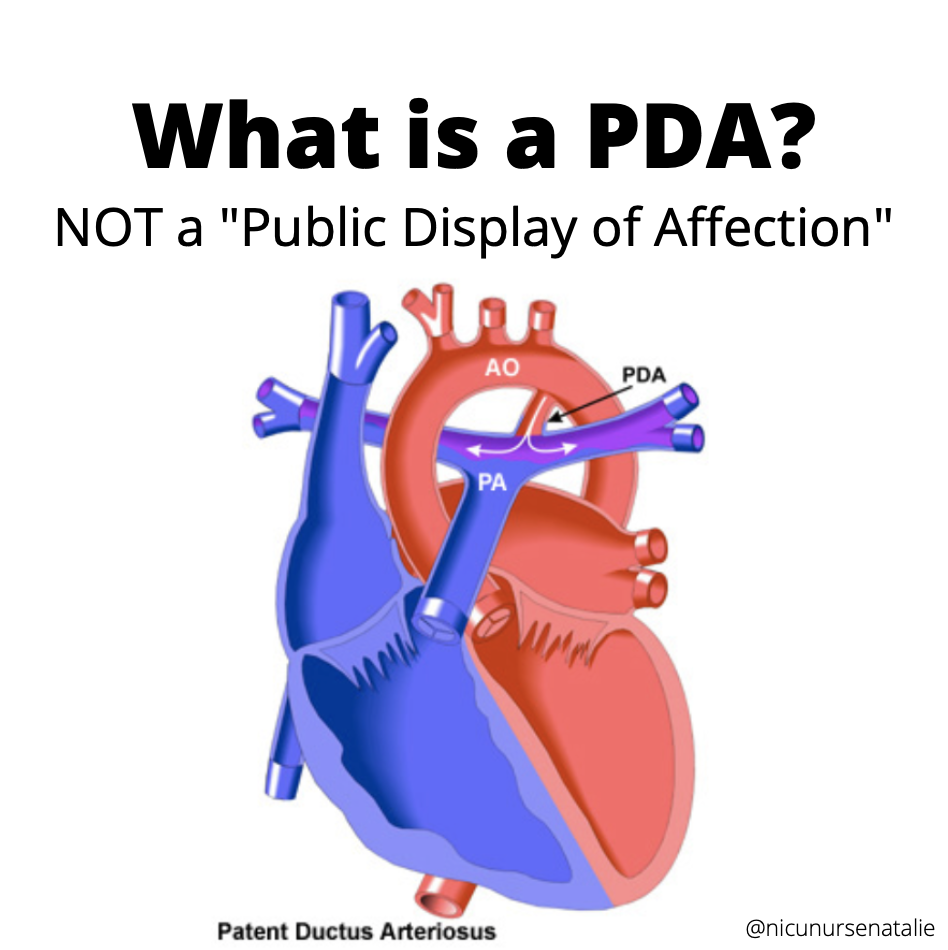

What is this PDA and why do the doctors want to close it

Let s Talk PDA THE NURSE NATALIE

What is PDA in Newborn Babies

What is PDA in Newborn Babies